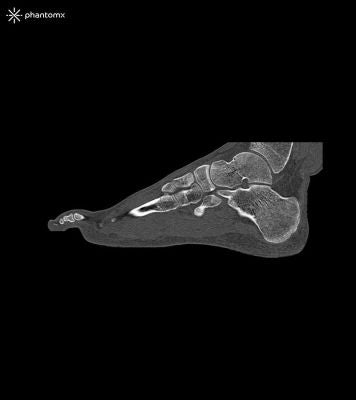

This phantom is created from real patient data and is manufactured using the latest technology. Bones, vessels and soft tissue are displayed authentically with realistic CT values for all tissues at 120 kVp tube voltage in the CT. If the phantom is to be used primarily with other tube voltages (e.g. 100 kVp), the calibration of the CT values can be adjusted accordingly if required. The phantom provides realistic tissue contrasts in X-ray imaging. Air spaces are filled by a material with about -80 Hounsfield units.

The foot phantom provides an extremely realistic simulation of a foot. Pathologies (e.g. fractures, calcifications, bones and soft tissue tumors) can be integrated on request.